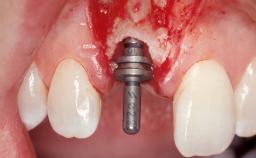

Immediate Flapless Placement of an Implant in a Maxillary Left Central Incisor Site

A 29-year-old female patient presented for treatment to replace the upper left central incisor tooth with an implant- supported restoration. The tooth had been intermittently symptomatic for the previous 12 months. The tooth had originally suffered trauma about 15 years previously. Several endodontic treatments had been performed, including an apicectomy procedure to retain the tooth. The patient was healthy and a non-smoker. She had reasonable expectations in regard to esthetic outcomes and the risk of marginal tissue recession following treatment. At medium smile, the gingival margins of the upper teeth were visible, with a display of 3 to 4 mm of the gingival margins. Gingival recession of tooth 21 and a discrepancy in the gingival levels between teeth 11 and 21 was observable during normal speech and smile.

Placement Protocol Immediate implant placement

Socket Morphology Single-root socket

Socket Integrity Damage to one or more bone walls

Bone Volume Damage to one or more socket walls